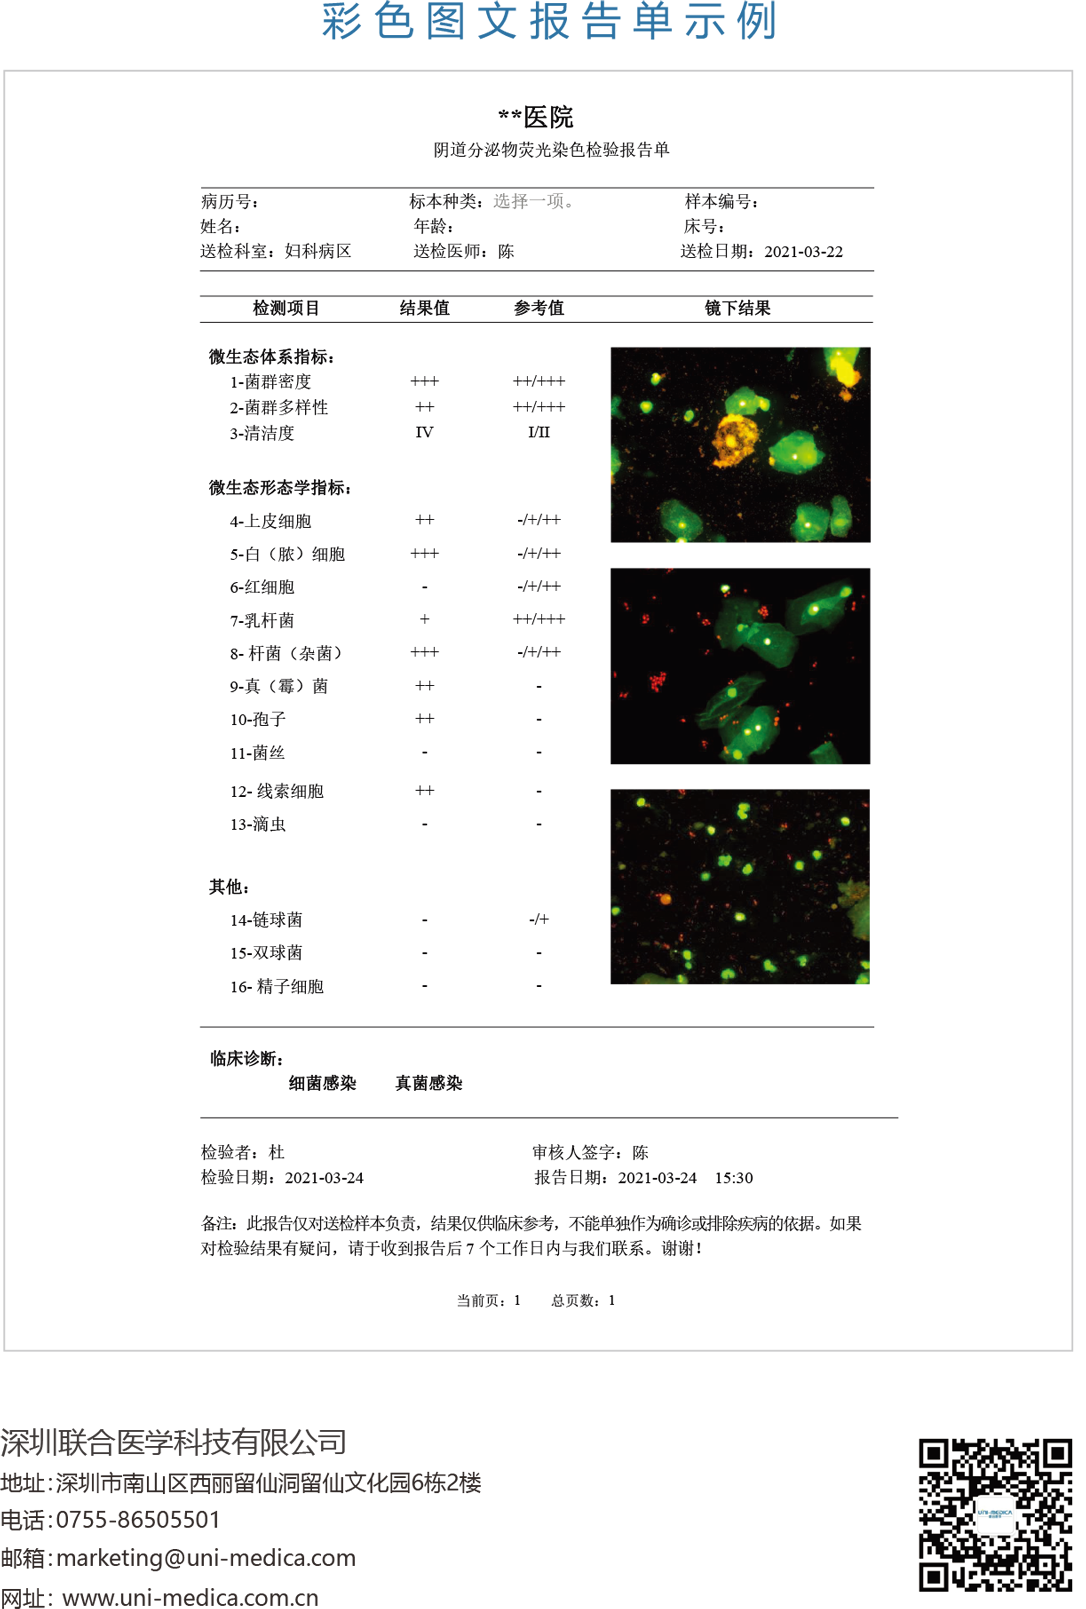

免疫荧光法结果展示及判读示例

阴道分泌物多重免疫荧光染色技术,具备形态学与荧光学的双重优势。可以同时对上皮细胞,白细胞,乳酸杆菌,线索细胞,念珠菌和毛滴虫等进行染色区分,既能检测阴道相关病原体感染,也能评估其阴道微生态和阴道清洁度等是否正常,为临床的快速诊断和治疗提供帮助。

上皮细胞/白细胞

绿色荧光

上皮细胞:作为内质控

白细胞:判定炎症程度

(清洁度)